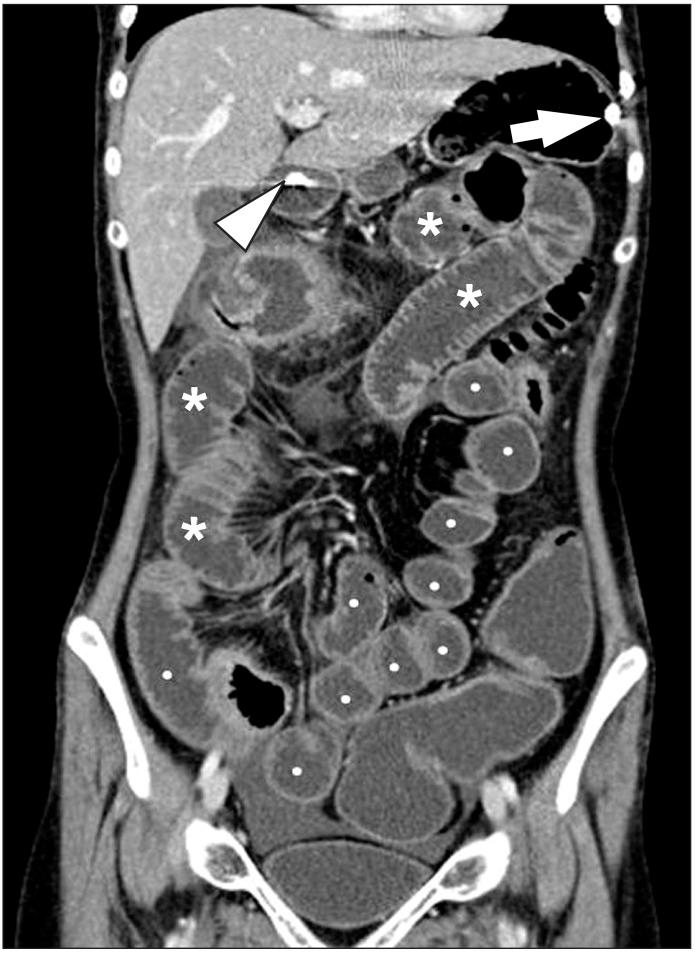

Imaging of the small bowel is complicated by its length and its overlapping loops. Recently, however, the development of crosssectional imaging techniques, such as computed tomography enterography (CTE) and magnetic resonance enterography (MRE) has shifted fundamental paradigms in the diagnosis and management of patients with suspected or known Crohn's disease (CD). CTE and MRE are noninvasive imaging tests that involve the use of intraluminal oral and intravenous contrast agents to evaluate the small bowel. Here, we review recent advances in each cross-sectional imaging modality, their advantages and disadvantages, and their diagnostic performances in the evaluation of small bowel lesions in CD.